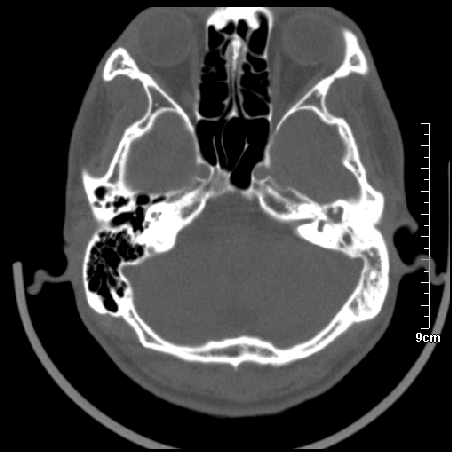

病例1

m/46y 头晕.耳鸣半月余 有乳突炎病史

左侧板障型乳突。

左侧慢性中耳炎伴胆脂瘤形成。